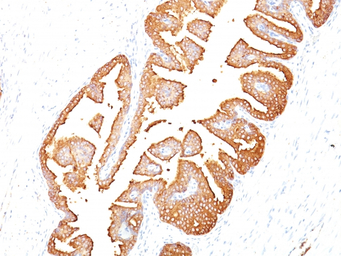

IHC-P analysis of human prostate carcinoma tissue using GTX34990 PSA antibody [KLK3/801].

Recognizes a single protein of 33-34kDa, identified as the prostate specific antigen (PSA). This MAb is highly specific to PSA and stains prostatic secretory and ductal epithelium in both normal and neoplastic tissues.